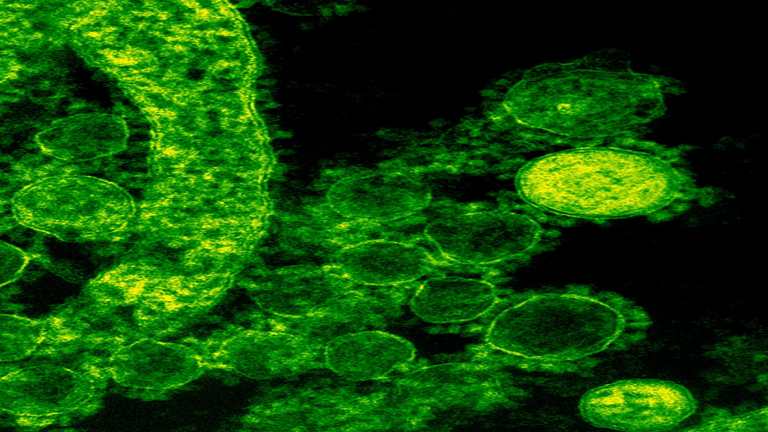

دراسة تكشف عن "الناقلين الفائقين الصامتين" لفيروس كورونا وسط تحذير العلماء!

أظهرت دراسة جديدة أن الأطفال هم "ناشرون فائقون صامتون'' لـ "كوفيد-19"، ويمكن أن يحملوا كميات أكبر من الفيروس مقارنة بالبالغين، ومع ذلك لا تظهر عليهم أي أعراض.